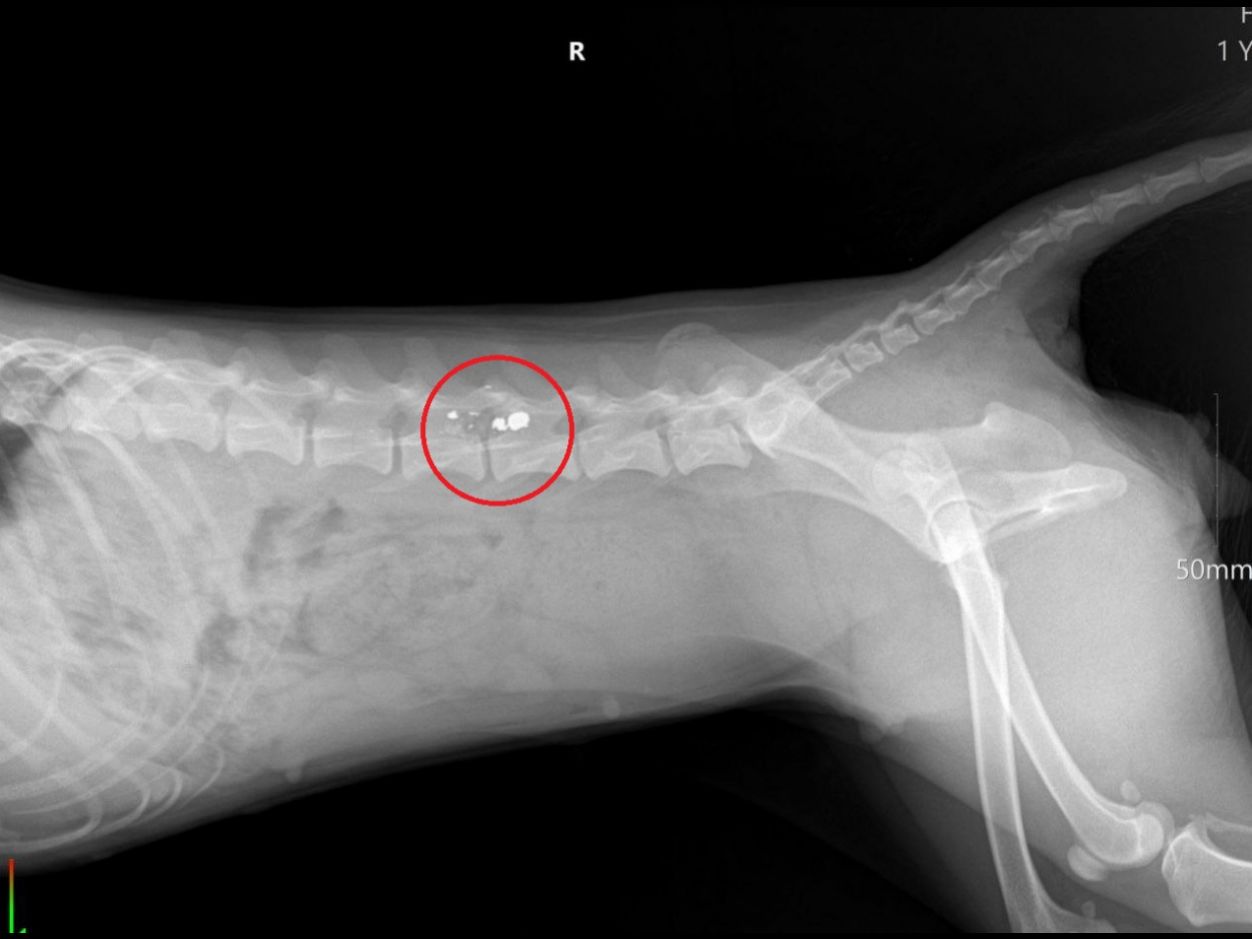

Хозяева доставили собаку в ветеринарную клинику. Врачи диагностировали травмы, которые привели к параличу задних лап.